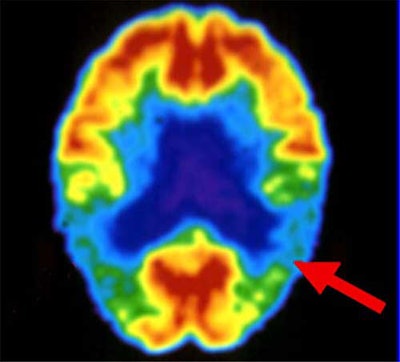

Jack joins a growing number of radiologists who believe they will someday screen for the disease in elderly people with memory loss or a family history of Alzheimer's. But consensus stops at the choice of modality. Some favor FDG-PET, which detects Alzheimer’s based on metabolic anomalies. Others favor MRI, either structural, which targets anatomic changes in the brain; or functional, which homes in on telltale brain activation patterns.

With 20 years of research to draw from, PET researchers are beginning to publish some convincing numbers. In a study presented at last year’s Society of Nuclear Medicine meeting, UCLA's Silverman and colleagues compared the results of 70 PET scans with autopsy-confirmed diagnoses. PET’s sensitivity in confirming Alzheimer’s was 96%.